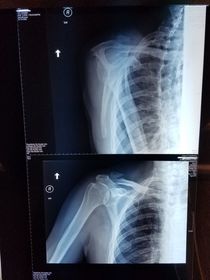

Which projections/positions are these? (top->bottom) TOP: Scapular Y-View _________________________ BOTTOM: AP External Rotation (greater tubercle in profile)

Which projection/position is this? Transthoracic Shoulder ___________________ ribs are blurred out from orthostatic breathing